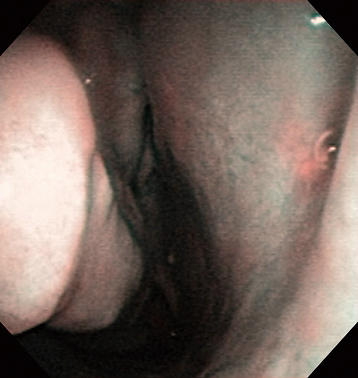

Right Epistaxis (Thrombocytopenia) Aged 80, male

white light

NBI

Comment:

The white light imaging suggested that the right epistaxis was bleeding from the middle meatus side of the middle nasal turbinate, and NBI was used to identify the deeper vessels.

Images and comments by Dr. S. Takano <ENF-V2>